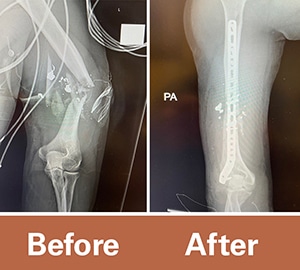

Sam was transferred from Kingwood to the Texas Medical Center as an acute trauma patient where a team of UT Physicians orthopedic surgeons stepped in. Sam arrived with an open humeral shaft fracture and severe bone injury that shattered his humerus, according to Stephen Warner, MD, PhD, orthopedic surgeon and assistant professor in the Department of Orthopedic Surgery at McGovern Medical School at UTHealth Houston.

Warner rebuilt Sam’s humerus in a tedious procedure that involved plates and 14 screws in his upper arm bone. That needed to heal before some of the other procedures could be done. The surgeons were initially called to manage his gunshot wounds but later discovered his radial nerve was transected by the bullet fragments and prevented him from extending his fingers or wrist.